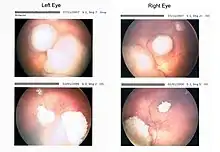

Funduscopic finding of a retinoblastoma

Ocular fundus aspect of retinoblastoma

Large exophytic white tumor with foci of calcification producing total exudative retinal detachment